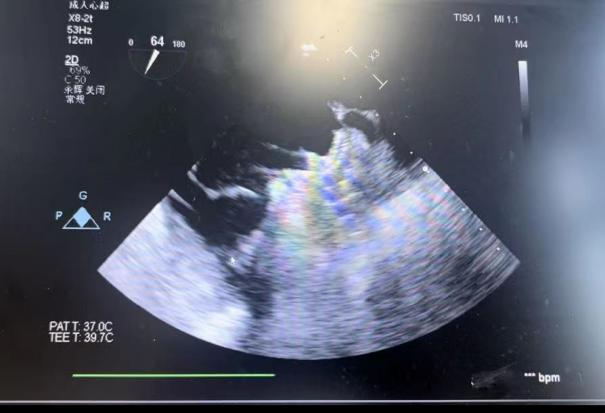

在食道超声引导下进行房间隔穿刺,由于心耳为反鸡翅型,穿刺位点需靠下靠前,潘教授先在90度双腔切面将定位靠下,再在45度主动脉短轴切面将定位靠前。穿刺成功后上导丝交换彩神在线网信彩票-彩神通免费版下载-彩神8争霸vlll-彩神购彩购彩大厅-彩神软件陆立根免费版-彩神ll争霸3-彩神ll彩神8-彩神ll争霸彩票-拼搏在线彩神网网页版LAnavi™分段控弯导引系统送至心耳口部,经过A、B双弯的调整使得鞘管轴向与心耳同轴,获得理想封堵位置。然后推送钢缆释放出固定盘,锚定后退鞘释放出封堵盘。超声下观察贴合良好,无明显残余分流,牵拉测试稳定,即释放左心耳封堵器。释放后再次通过超声各个角度进行验证,封堵结果完美有效,整个过程一气呵成,手术取得了极大的成功。

牵拉测试稳定 完美有效封堵